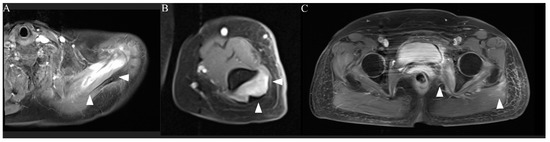

- Lamminen, A.E.; Hekali, P.E.; Tiula, E.; Suramo, I.; Korhola, O.A. Acute rhabdomyolysis: Evaluation with magnetic resonance imaging compared with computed tomography and ultrasonography. Br. J. Radiol. 1989, 62, 326–330. [Google Scholar] [CrossRef]

- Shintani, S.; Shiigai, T. Repeat MRI in acute rhabdomyolysis: Correlation with clinicopathological findings. J. Comput. Assist. Tomogr. 1993, 17, 786–791. [Google Scholar] [CrossRef] [PubMed]

- Lu, C.H.; Tsang, Y.M.; Yu, C.W.; Wu, M.Z.; Hsu, C.Y.; Shih, T.T.F. Rhabdomyolysis: Magnetic Resonance Imaging and Computed Tomography Findings. J. Comput. Assist. Tomogr. 2007, 31, 368–374. [Google Scholar] [CrossRef]